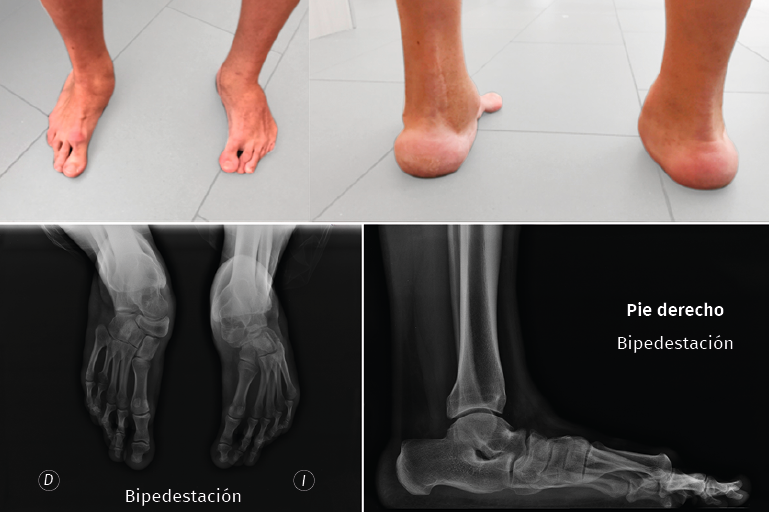

La hipercorrección tras una liberación posterointerna es un problema descrito en la literatura y de difícil resolución. Clásicamente, el tratamiento con triple artrodesis era el más extendido(11), pero la insuficiencia del gastrosóleo no tiene modo quirúrgico de tratarse y la táctica de abordaje de este reto precisa entender que estos pacientes suelen presentar un pie plano con desplazamiento dorsal del primer radio (bunion dorsal metatarsofalángico) y el ápex del descenso del mediopié casi siempre se halla en el cuneiforme medial o en la 1.ª ATMT. Después de evaluar de este modo la deformidad, las autoras proponen la realización de una osteotomía para descender el primer radio, idealmente una osteotomía de cierre con base plantar en el primer cuneiforme mediante osteosíntesis y valorar transponer o no el tibial anterior según la supinación que presente (Figura 5).

Figura 5. Hipercorrección. Imagen clínica de la hipercorrección en el pie derecho y deformidad combinada en el izquierdo en un paciente varón de 36 años, intervenido con liberaciones posterointernas en ambos pies en la infancia. Radiográficamente, en el pie derecho se aprecia el ascenso del primer radio y cómo la primera articulación tarsometatarsiana o el cuneiforme medial son el ápex de la convexidad plantar.